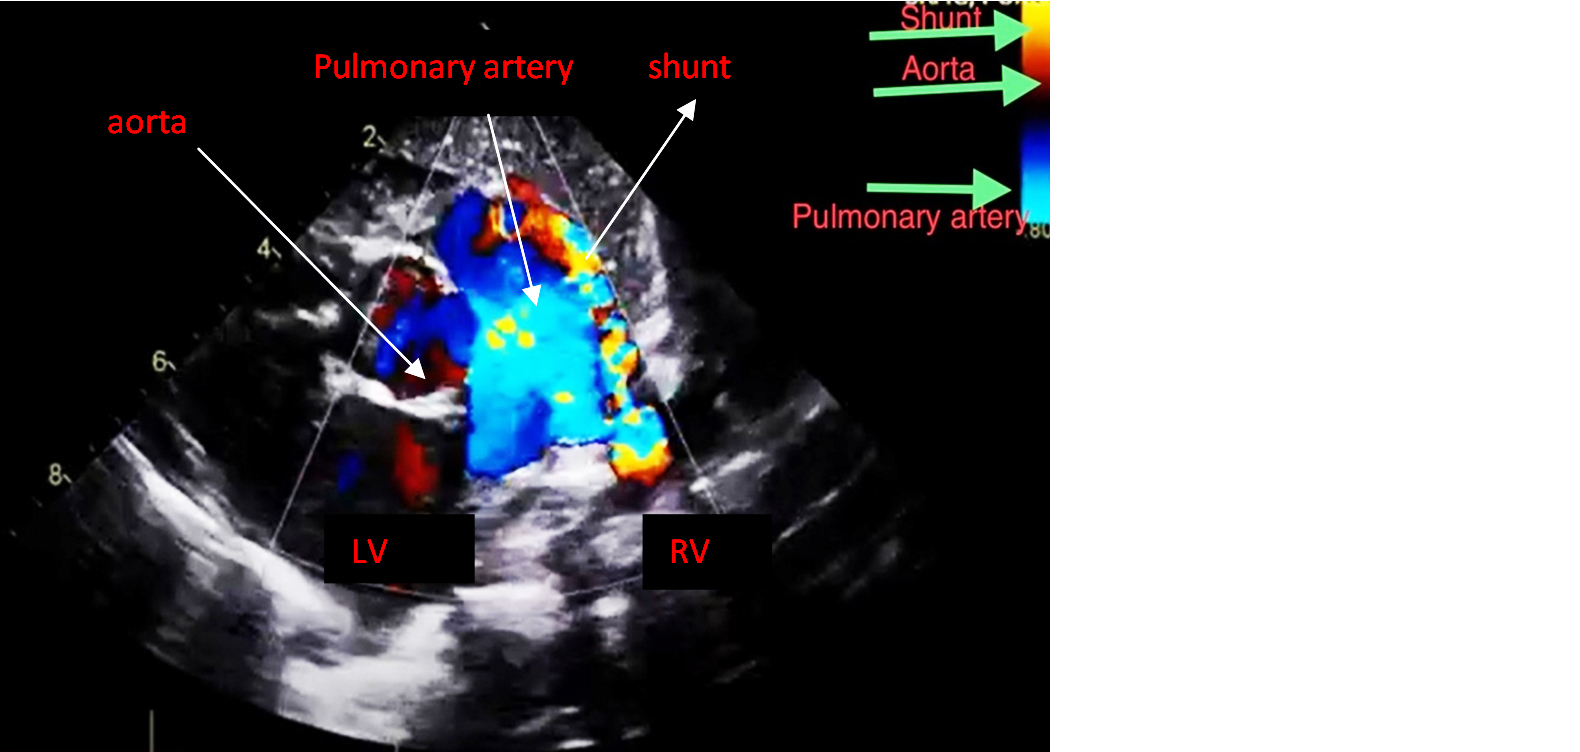

An echocardiogram revealed a patent ductus arteriosus with a residual shunt across the device. Normal left aortic arch, good biventricular function, no pericardial effusion (Figures 1 and 2). RT PCR was negative for COVID-19. Hematological investigations were within the normal range.

Figure 1: Echocardiogram showing the Patent ductus arteriosus.